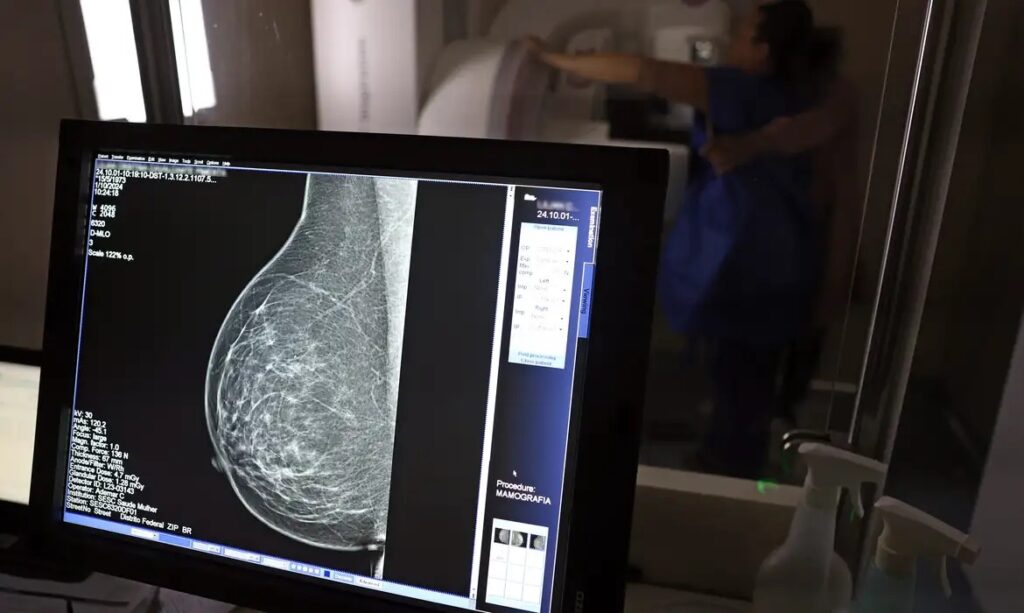

O direito já estava incluído na CLT desde 2018. A partir de agora, as empresas passam a ser obrigadas a divulgar essa informação, além de outras relacionadas a campanhas oficiais de vacinação contra o HPV e sobre o acesso a serviços de diagnósticos de cânceres de mama, próstata e de colo do útero.

O texto estende o uso das folgas também para a realização de exames preventivos do HPV, além dos de câncer que já estavam previstos na legislação anterior. A a Lei 15.377 foi sancionada pelo presidente Luiz Inácio Lula da Silva, e publicada na edição do Diário Oficial da União (DOU).